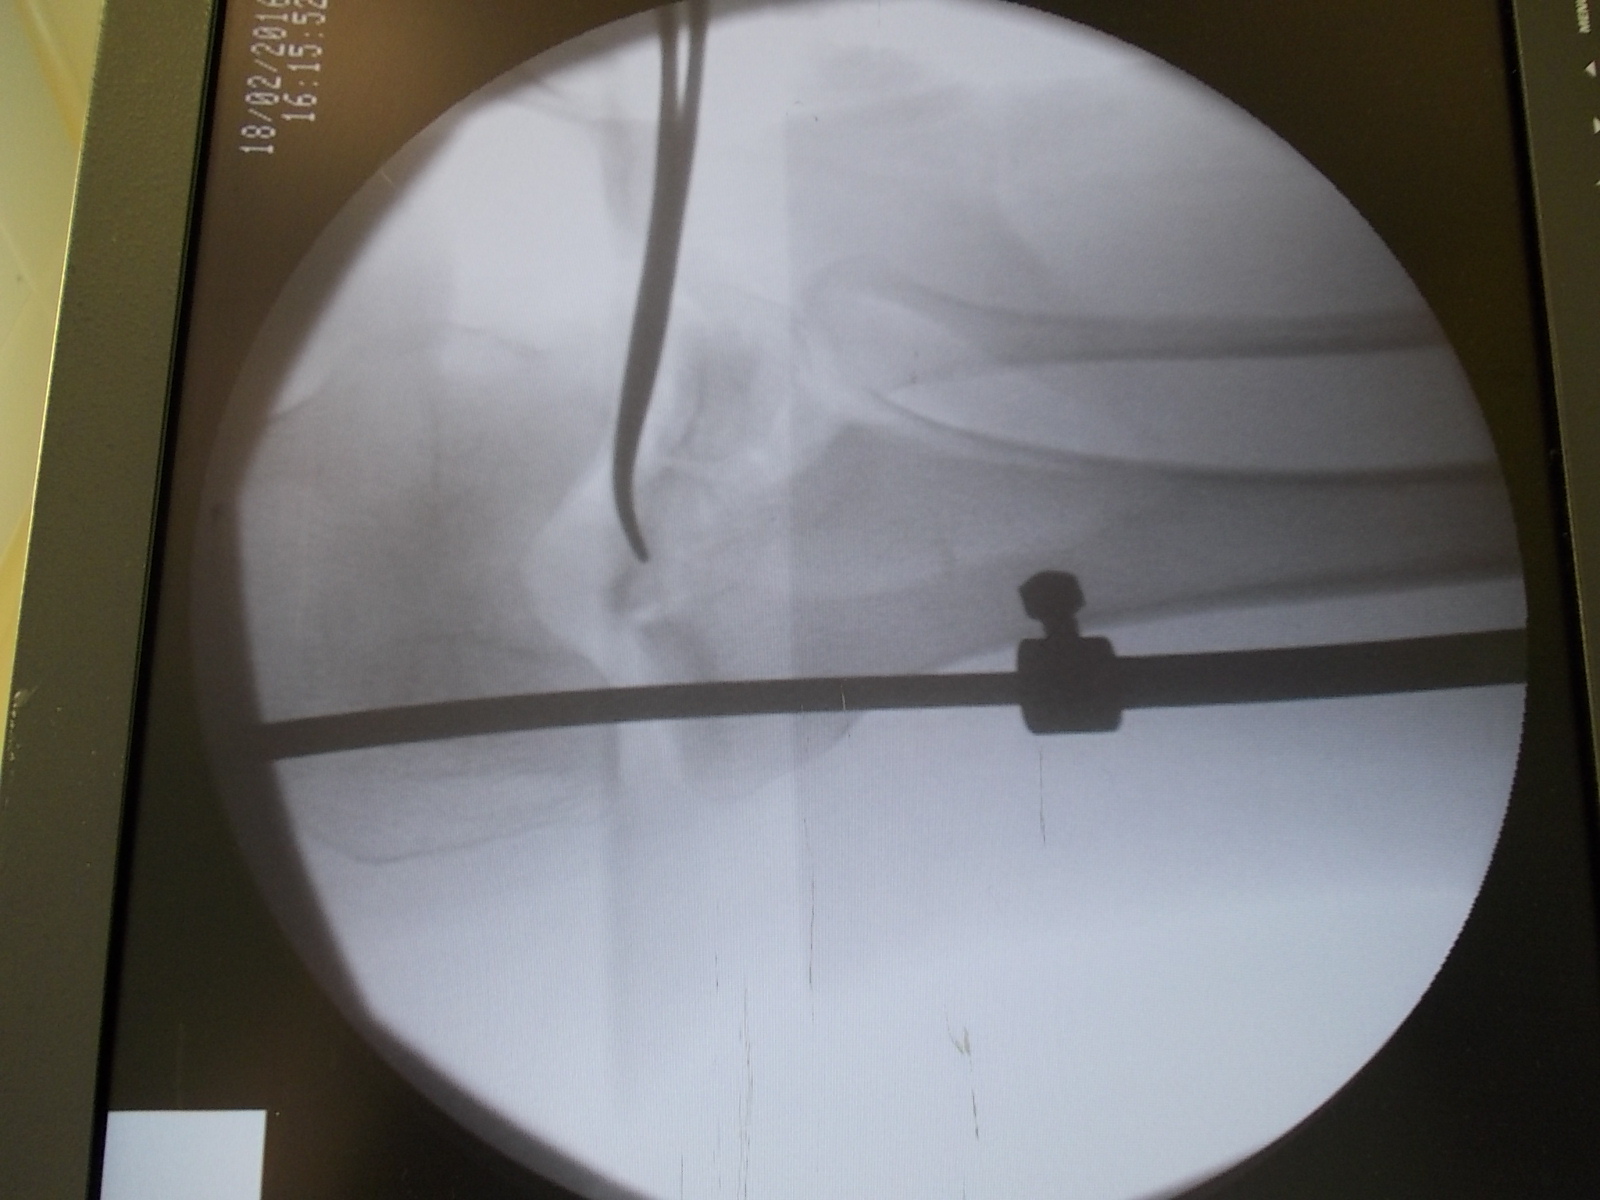

Операция - открытая репозиция, остеосинтез большеберцовой кости опорной пластиной с костной ксенопластикой маетриалом "Остеоматрикс". На контрольных снимках в три и шесть месяцев имеется консолидация перелома, миграции фиксатора нет, имеется остеоинтеграция ксенопластического материала. Функция коленного сустава полная.

Отдаленные результаты через 3 (три) месяца

Отдаленные результаты через 6 (шесть) месяцев

Отдаленные результаты через 14 (четырнадцать) месяцев